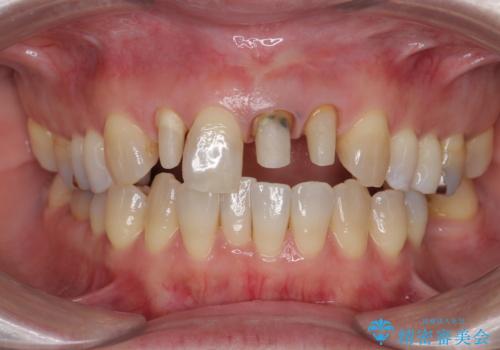

- 前歯のクラウンの歯肉の位置が年々変化し、歯ぐきのフチが黒くなってしまった、綺麗にしたいと希望されて来院されました。

装着されているセラミッククラウンを除去したのち、現在の歯ぐきのラインにしっかりと合う精度の高いオールセラミッククラウンを作製していきます。